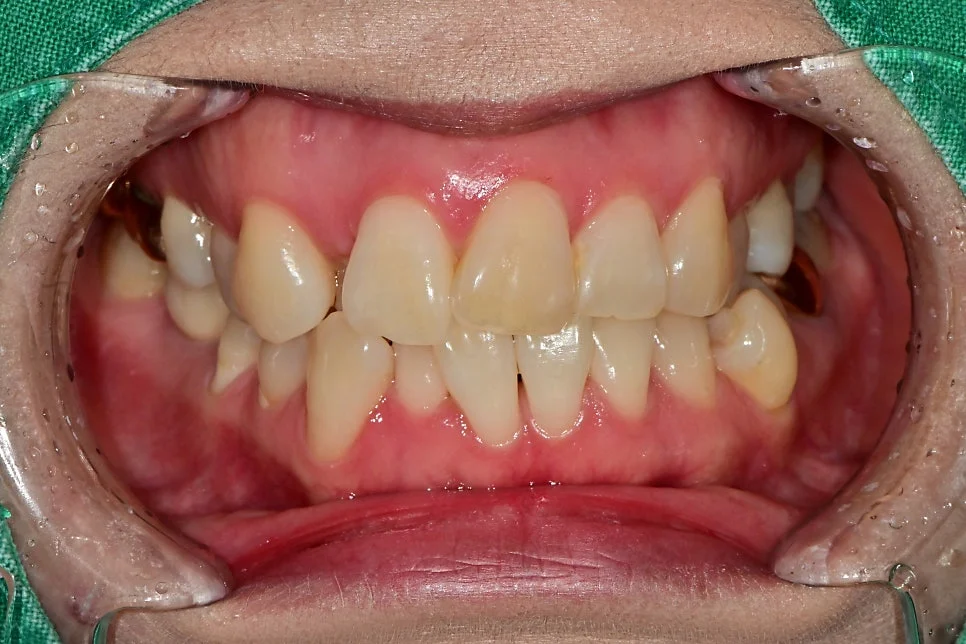

환자 초진 구강 사진 — 전체적인 치아 상태 확인

오른쪽 아래의 충치 진단

오른쪽 아래를 살펴보니 임플란트와 바로 앞 치아 사이에 벌어진 틈이 보입니다!